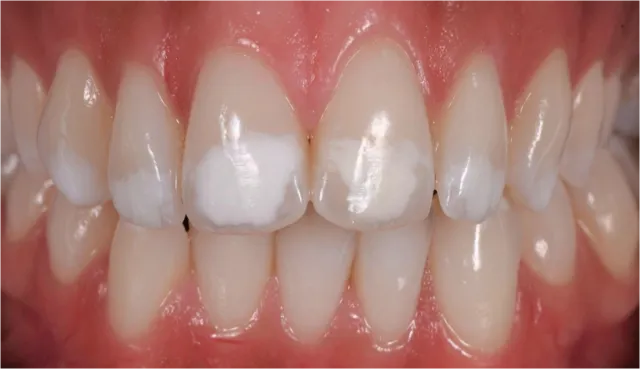

经抛光, 治疗结果令人满意并且印象深刻 (Fig. 7 and 8)。